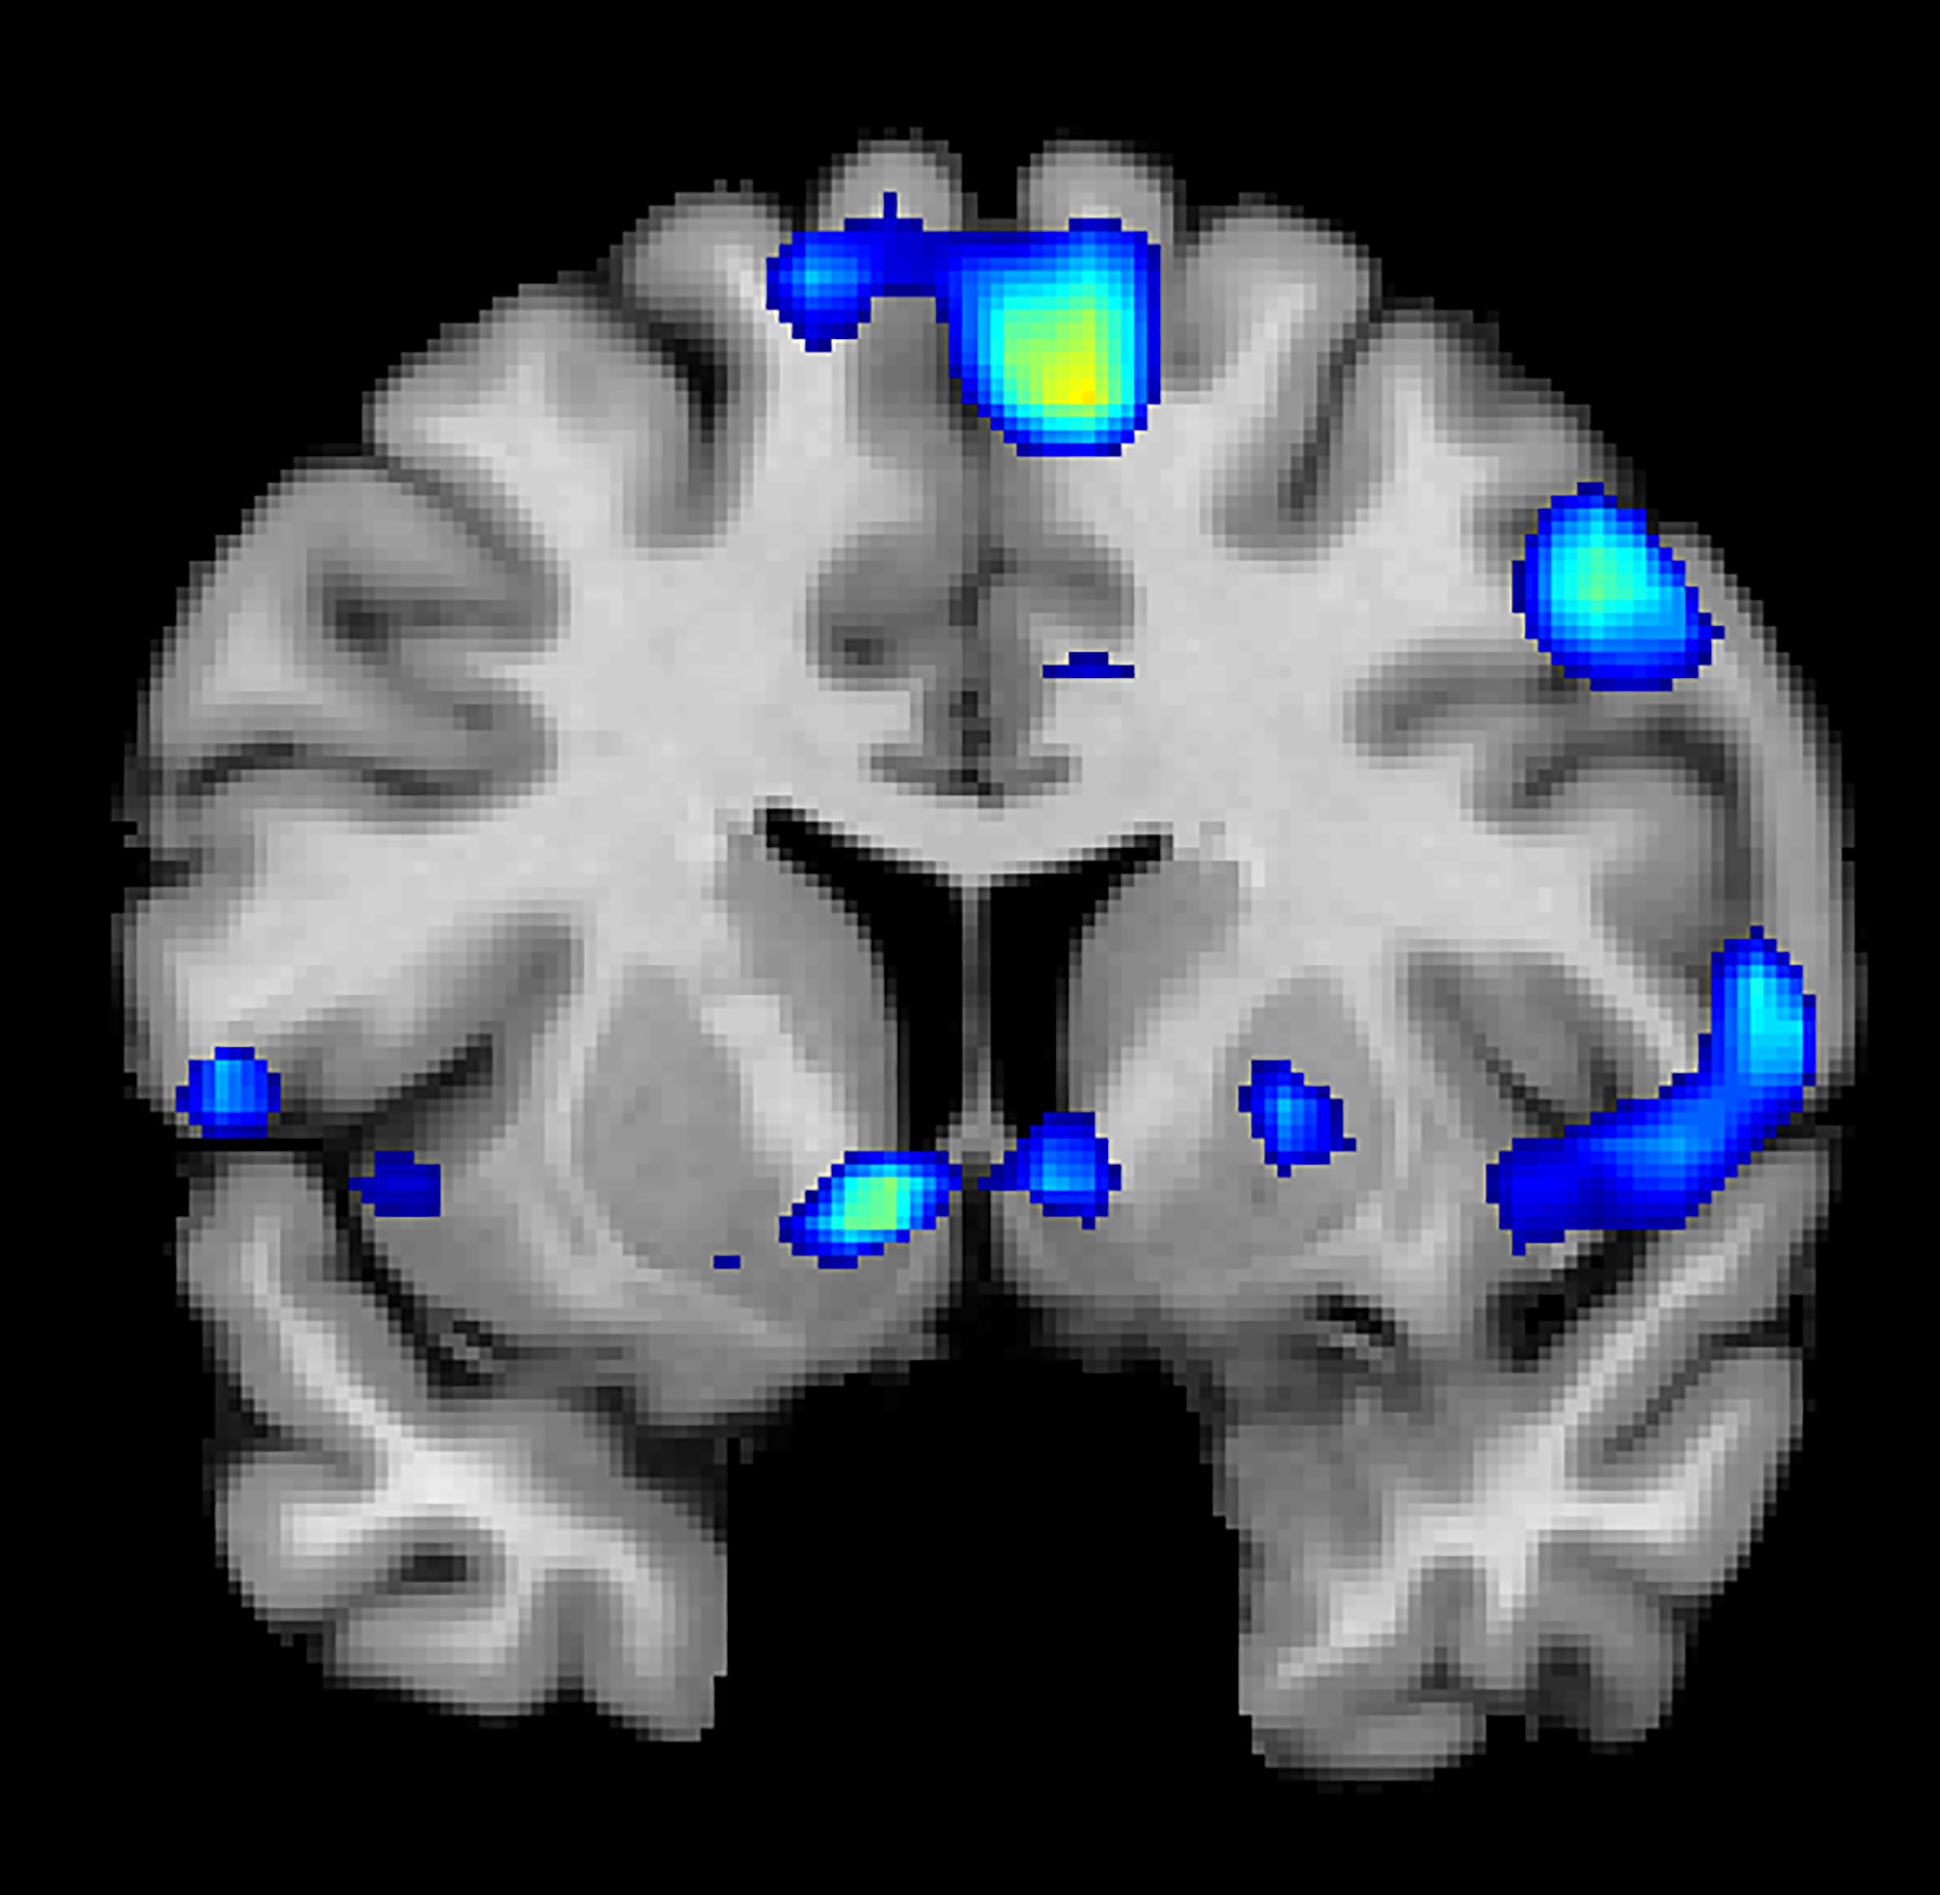

La exploración de fMRI de los sujetos participantes en el estudio muestra regiones del cerebro que se vuelven activas cuando los participantes tienen una experiencia espiritual, incluyendo un centro de recompensa en el cerebro, el núcleo accumbens, un grupo de neuronas del encéfalo a las que se atribuye una función importante en el placer y el sistema de recompensa.

Basados en las exploraciones de fMRI, los investigadores descubrieron que los sentimientos espirituales activan el núcleo accumbens, una región crítica del cerebro para procesar la recompensa. El circuito de recompensa es un grupo de estructuras neuronales del cerebro relacionado con el deseo, el placer y el refuerzo positivo.

La actividad de pico ocurrió aproximadamente 1-3 segundos antes de que los participantes pulsaran el botón y se repitió en cada una de las cuatro tareas. Cuando los participantes experimentaban picos de intensidad en sus sentimientos, sus corazones latían más rápido y su respiración se había más profunda.

Además de los circuitos de recompensa del cerebro, los investigadores descubrieron que los sentimientos espirituales estaban asociados con la corteza prefrontal media, una región cerebral compleja que se activa mediante tareas que incluyen valoración, juicio y razonamiento moral. Los sentimientos espirituales también activaron las regiones cerebrales asociadas con la atención focalizada.